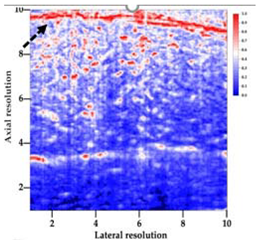

3.3. B-Mode Images

3.5. Echogenicity

4.1. Ultrasonography and Aerogel Dimensional Analyis

| Aerogel Type | US Image | Normalized Intensity Map | 3D Intensity Map | |

|---|---|---|---|---|

| 1 | Muscle |  |  |  |

| 2 | X-silica |  |  |  |

| 3 | X-silica-La2O2S:Eu |  |  |  |

| 4 | SMPU-Mix-14 |  |  |  |

| 5 | SMPU-Mix-18 |  |  |  |

| 6 | BRF-CA |  |  |  |

| 7 | ARF-CA |  |  |  |

| 8 | X-Ca-Alg-2 |  |  |  |

| 9 | X-Ca-Alg-1 |  |  |  |

| Aerogel Type | Imaging Frequency (MHz) | Optimal Frequency (MHz) | Echogenicity | Image Characteristics | Impedance Mismatch (%) | |

|---|---|---|---|---|---|---|

| Subcutaneous | Submuscular | |||||

| X-silica | 6.5–13.4 | 13.4 MHz | Hypoechoic | Least Hyperechoic | Distinct linear boundary | 92.03 |

| X-silica-La2O2S:Eu | 6.5–13.4 | 13.4 MHz | Hypoechoic | Least Hyperechoic | Distinct linear boundary | 90.28 |

| SMPU-Mix-14 | 6.5–13.4 | 11 MHz | Hyperechoic | Moderately Hyperechoic | Irregular boundary | 98.33 |

| SMPU-Mix-18 | 6.5–13.4 | 11 MHz | Hyperechoic | Moderately Hyperechoic | Irregular boundary | 98.23 |

| BRF-CA | 6.5–13.4 | 13.4 MHz | Hyperechoic | Hyperechoic | Waterfall appearance | 97.16 |

| ARF-CA | 6.5–13.4 | 13.4 MHz | Hyperechoic | Hyperechoic | Waterfall appearance | 97.12 |

| X-Ca-Alg-2 | 6.5–13.4 | 11 MHz | Isoechoic | Strongly Hyperechoic | Irregular boundary | 98.03 |

| X-Ca-Alg-1 | 6.5–13.4 | 11 MHz | Isoechoic | Strongly Hyperechoic | Irregular boundary | 97.97 |